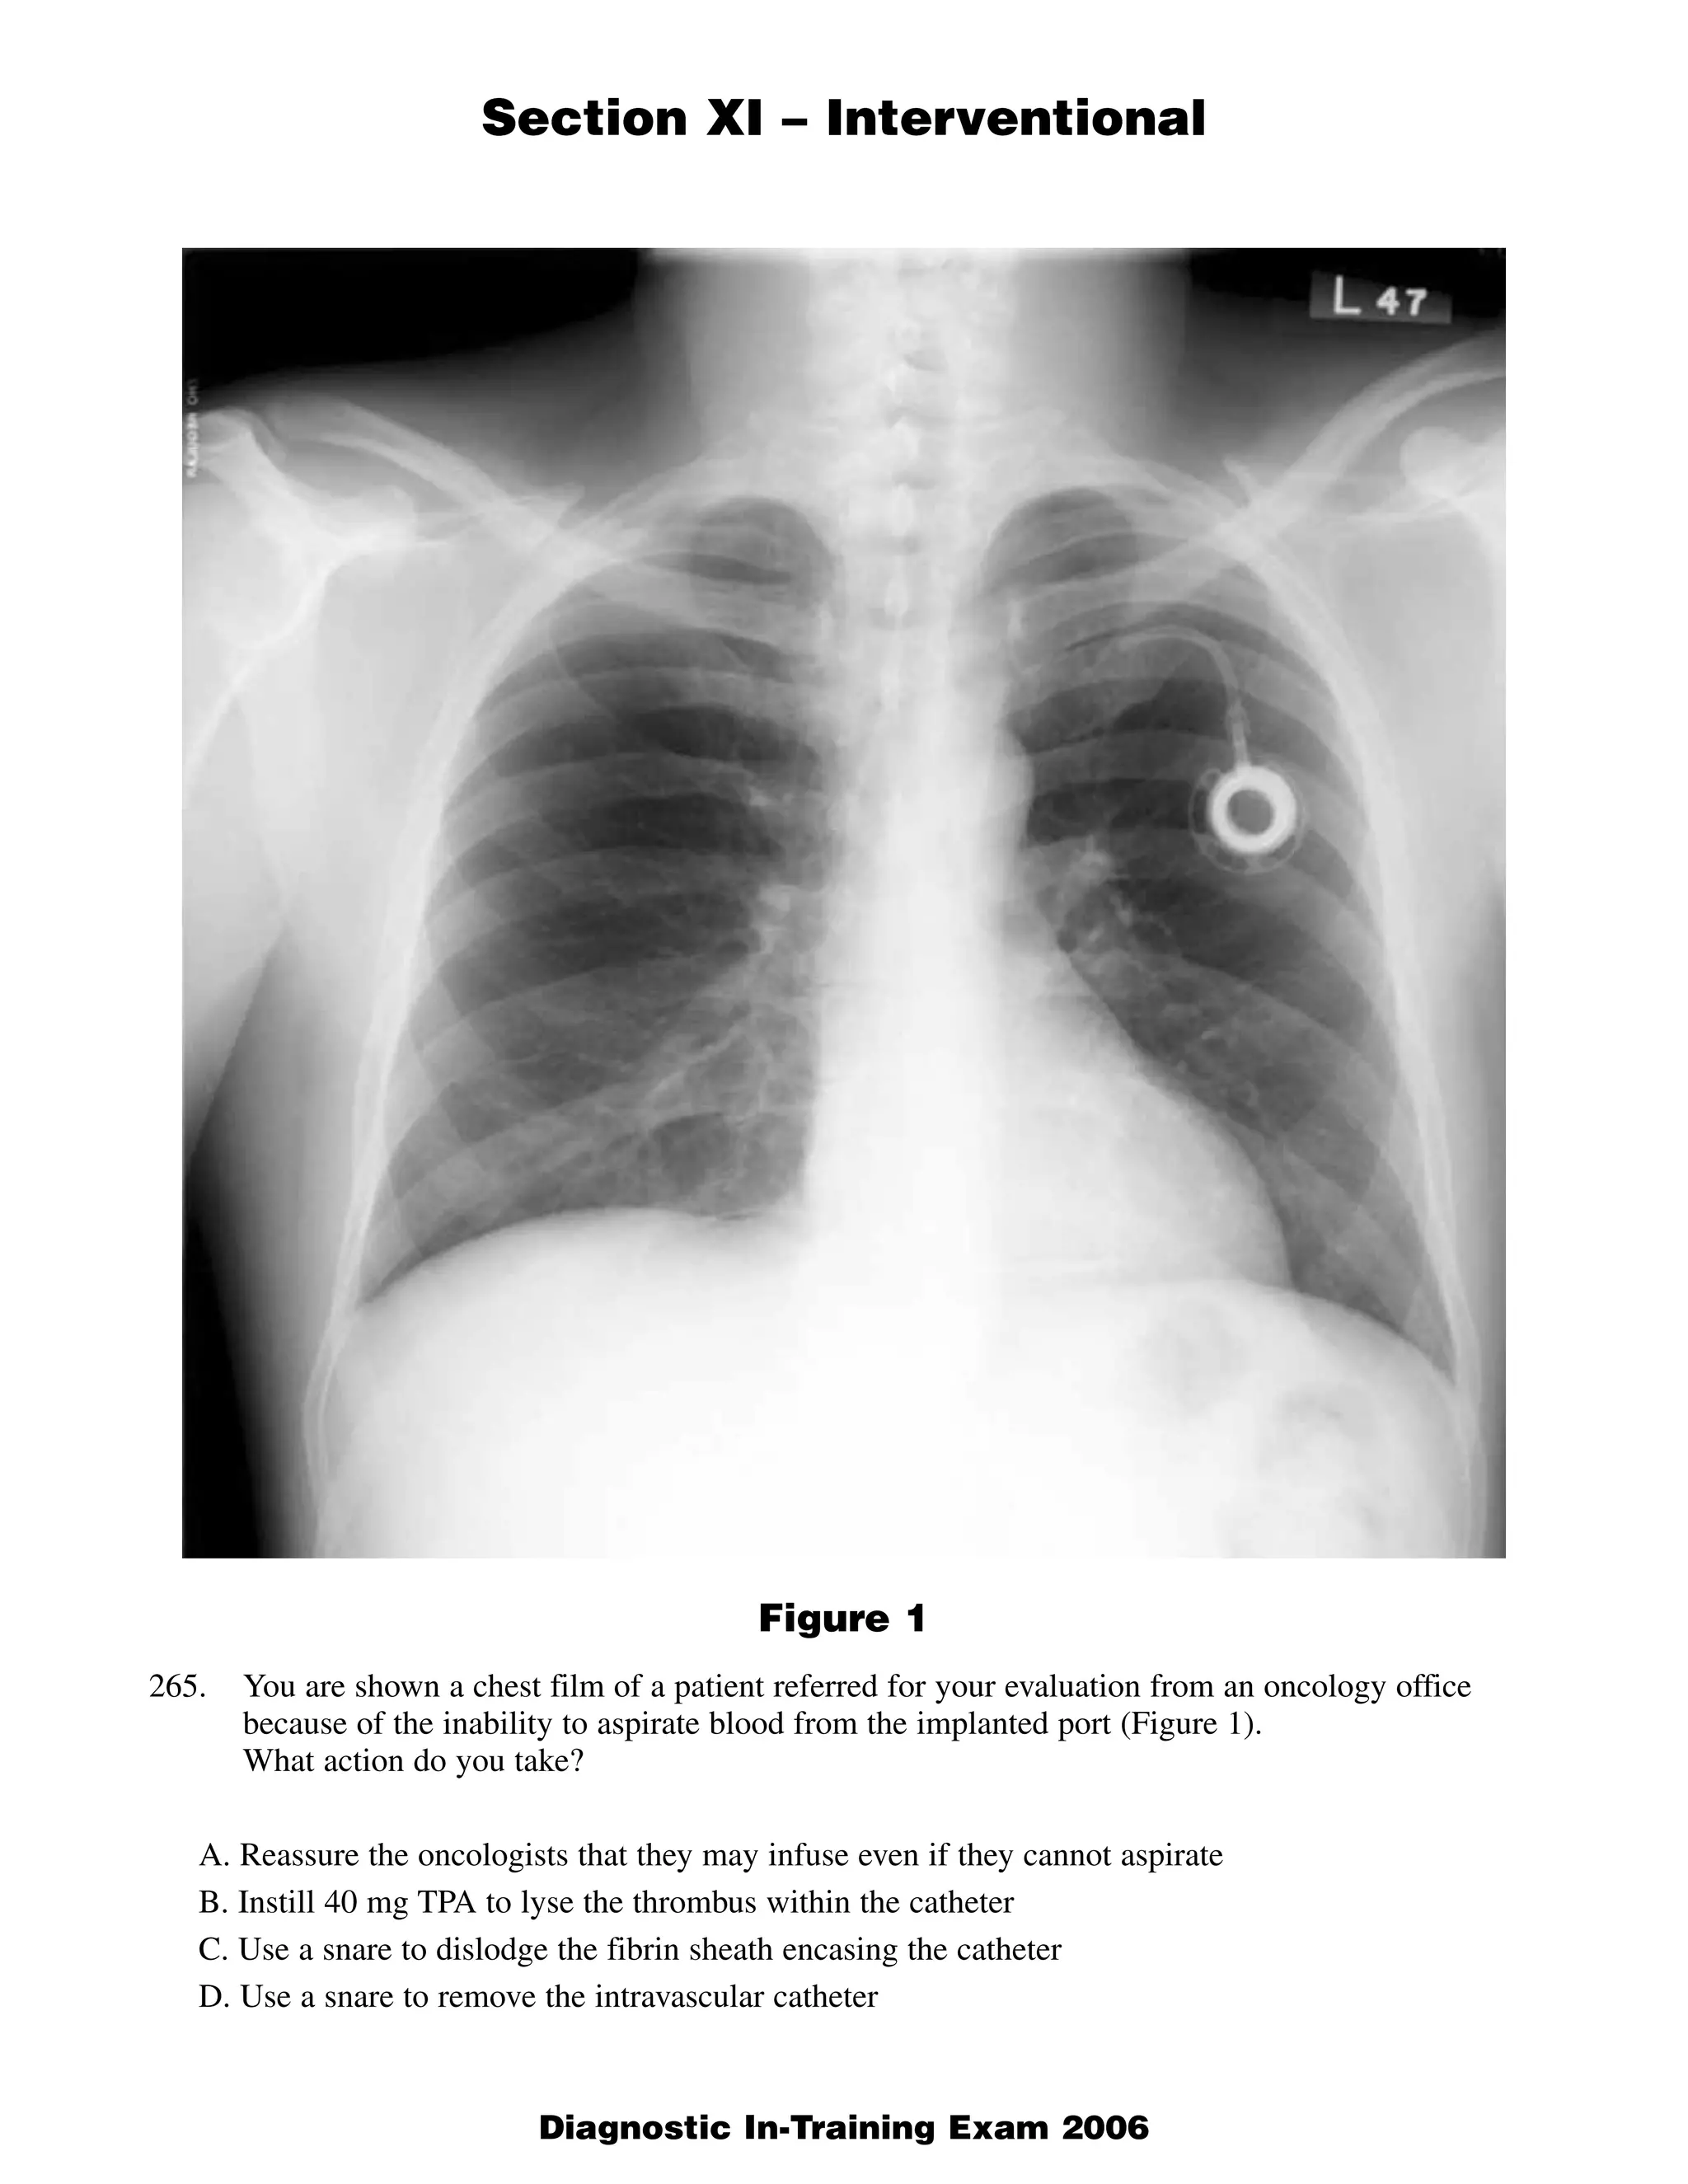

This document contains 5 clinical case scenarios involving interventional radiology procedures (questions 265-269). Each case is accompanied by an image and 4 possible answers. The correct answer is identified and a brief rationale is provided for each case. Question 270-279 continue testing knowledge of interventional radiology with additional multiple choice questions related to procedures, techniques, and disease processes.